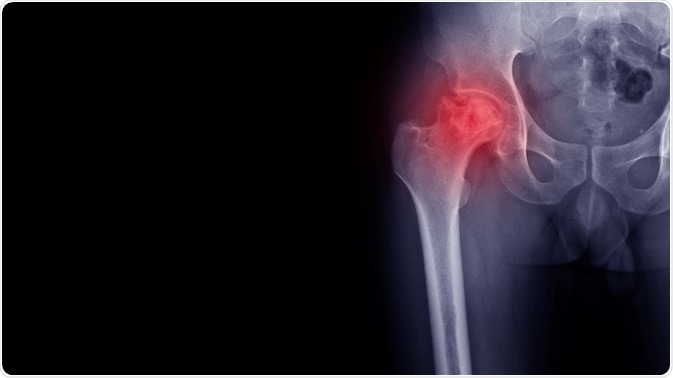

Osteoarthritis (OA) is a major cause of pain and disability in daily life, and a heavy healthcare expense as well. Both of these can cause significant distress and psychosocial impact.